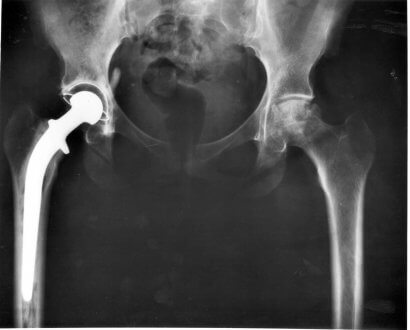

Operation af Hansen I

Selvom vi ikke kan rådgive om, hvor vidt det er en god idé at gennemgå operation, kan vi give dig de nødvendige oplysninger til selv at træffe beslutningen. For det første er det vigtigt at forstå, at ikke alle operationer virker. Der er imidlertid en relativt høj succesrate, når sygdommen diagnosticeres i tide.

Alt afhænger af hvad neurologen siger. Operationen kan undgås, hvis dyret stadig er i stand til at gå på trods af at have diskusprolaps, og hvis den professionelle siger, at diskussen kun stikker ud.

I så fald skal din hund gennemgå en seksugers behandlingsplan, der omfatter streng hvile, et supplement med kortikosteroider og en gastrisk beskytter.

Hvis du beslutter dig for at gennemføre operationen, bør du vide, at dyret skal have et par ugers total hvile. Chancerne for at kurere bagbensproblemer er høje.